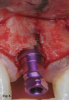

Typically, bone is cut prior to implant placement with the use of standard drill burs. While drill bits rotate, the cutting resistance vector has been described as "constantly changing," and this can cause the drill bit to shave along the bone surface away from the initial osteotomy site, inducing less-than-optimal site preparations (Figure 2 through Figure 4).37 Since fresh, hydrated trabecular bone is a ductile material, it has a good capacity for plastic deformation. Osseodensification is essentially a burnishing process that redistributes bone material on the bony surface through plastic deformation.37 The counterclockwise rotation of osseodensification burs causes the lands of the bur to slide across the surface of the bone by means of low plastic deformation that is purposefully designed to have a compressive force less than the ultimate strength of the bone.

Fig 2. Implant placement using standard burs may potentially lead to off-axis drilling, which at times may compromise implant outcomes or long-term esthetic results. These three photographs show examples of cases in which multiple implant threads were left exposed due to thin buccal bone relative to the implant placement (clinical photographs courtesy of Salah Huwais, DDS).

Figure 2

Fig 3. Implant placement using standard burs may potentially lead to off-axis drilling, which at times may compromise implant outcomes or long-term esthetic results. These three photographs show examples of cases in which multiple implant threads were left exposed due to thin buccal bone relative to the implant placement (clinical photographs courtesy of Salah Huwais, DDS).

Figure 3

Fig 4. Implant placement using standard burs may potentially lead to off-axis drilling, which at times may compromise implant outcomes or long-term esthetic results. These three photographs show examples of cases in which multiple implant threads were left exposed due to thin buccal bone relative to the implant placement (clinical photographs courtesy of Salah Huwais, DDS).

Figure 4